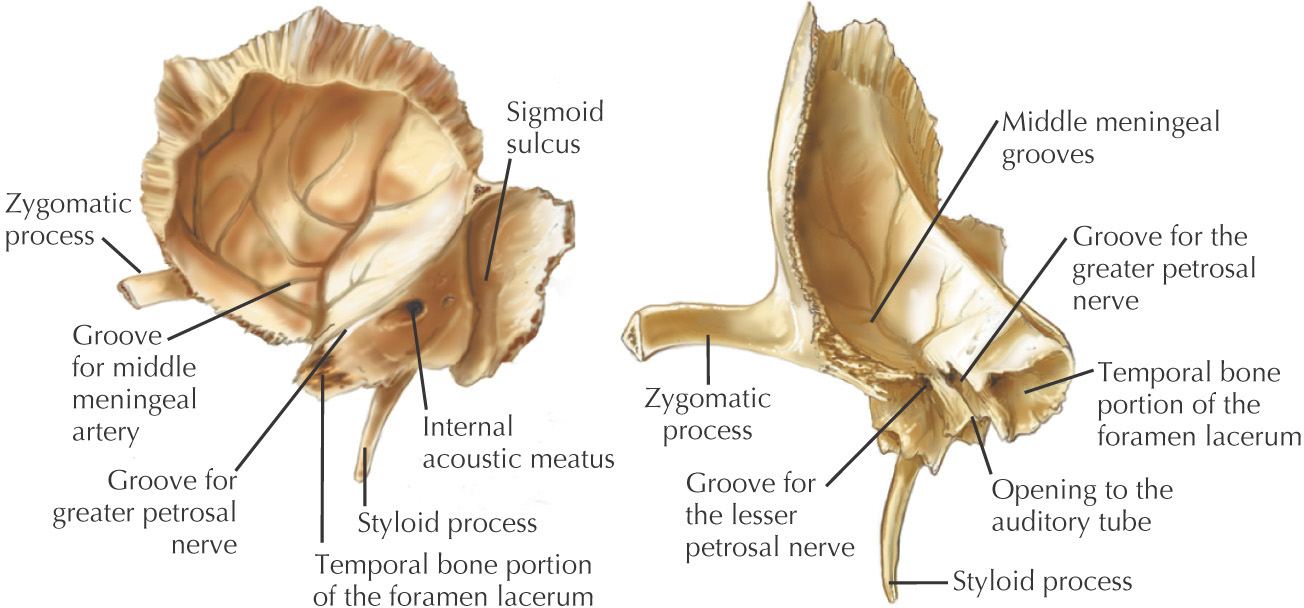

Анатомия и особенности фиссуры петротимпаника